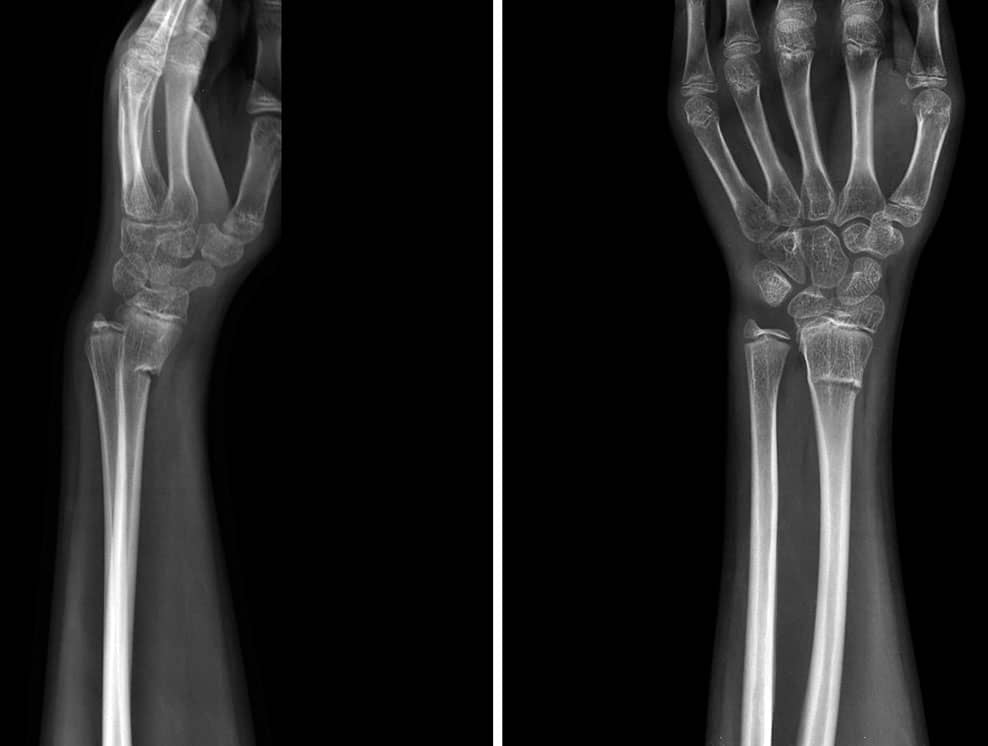

Punho – incidência PA – rotina básica

Justificativa para realização do exame

incidência realizada para o estudo de fraturas, luxações, subluxações e todas as articulações do punho e patologias, tais como artrose, artrite e osteomielite.

Principais estruturas demonstradas

o punho (carpo) em PA e regiões proximal de metacarpos e distal de antebraço, mais especificamente, o estudo dos processos estiloides de rádio e ulna.

Fatores técnicos e posicionamento:

DFF: 1m.

Tamanho do filme/receptor de imagem e sentido: 13x18cm ou 18x24cm no sentido transversal.

Técnica de referência: 4mAs e 40KV, fora do bucky.

RC: perpendicular ao receptor de imagem, direcionado para a porção média dos ossos carpais (meio da articulação do punho).

Posição do paciente e da parte ou região do corpo: colocar o paciente sentado na extremidade da mesa de exames com a mão e os punhos pronados e apoiados confortavelmente no receptor de imagens.

Punho – incidência Lateral – rotina básica

incidência realizada para o estudo de fraturas, luxações, subluxações e todas as articulações do punho e patologias, tais como: artrose, artrite e osteomielite.

o punho (carpo) em perfil e regiões proximal de metacarpos e distal de antebraço, além de fraturas isoladas nos processos estiloides de rádio e ulna.

Técnica de referência: 4mAs e 44KV, fora do bucky.

RC: perpendicular ao receptor de imagem, direcionado para a face lateral dos ossos carpais (meio da articulação do punho).

Posição do paciente e da parte ou região do corpo: colocar o paciente sentado na extremidade da mesa de exames com a mão e punhos lateralizados e apoiados confortavelmente no receptor de imagens.

Punho – incidência PA com desvio ulnar para escafoide – rotina especial

Incidência realizada para o estudo de fraturas e luxações do escafoide e do rádio distal e para análise da articulação radiocarpal.

O punho (carpo) em PA com foco de estudo no escafoide e na sua articulação com o rádio.

RC: perpendicular ao receptor de imagem, direcionado para o meio dos ossos carpais (meio da articulação do punho).

Posição do paciente e da parte ou região do corpo: colocar o paciente sentado na extremidade da mesa de exames com a mão e o punho pronados e com um desvio em direção à ulna (desvio ulnar), o suficiente que o paciente possa suportar ou tolerar sem erguer o antebraço.